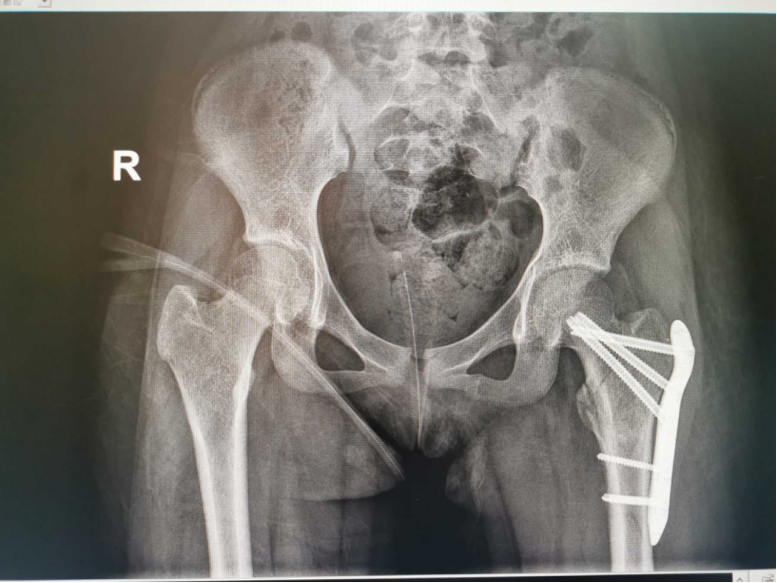

这是发生在2022年1月30日骨伤科病房的一幕。病床上小姑娘叫若琳(化名),是一位来自于广东罗定的12岁小姑娘,因为意外从高处跌落,导致腰椎骨折、髋部骨折、鼻骨骨折。面对复杂的多发骨折,加上家庭条件相对困难,若琳的父母心急如焚,经人联系,她从当地医院转被送到广州医科大学附属中医医院骨伤科救治。

骨伤科主任田天照副主任中医师第一时间组织专家进行全面评估,经过细致讨论,考虑到小女孩骨骺线未完全闭合,还有生长潜力,务必将手术对骨折生长发育的影响降到最低,科室最终制定了详细的治疗及护理方案。

经过手术,小若琳损伤最严重的髋部骨折得到了复位,良好的内固定位置既保证了骨折的稳定,又保留了骨骼发育的潜力。